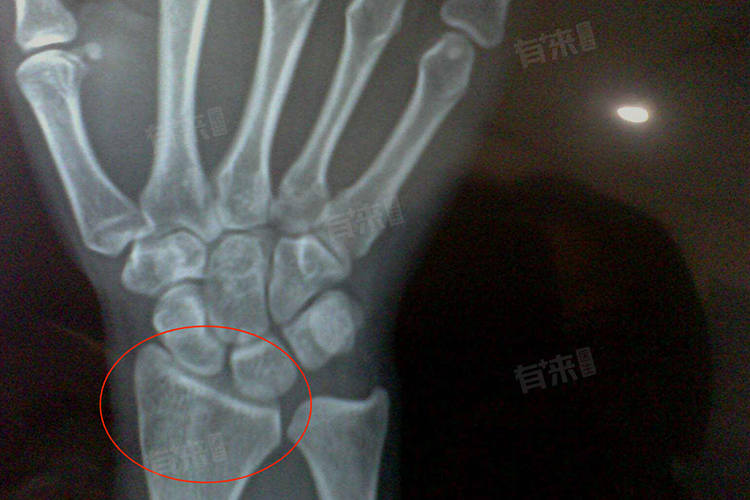

- 骨骺线闭合是骨骼生长发育过程中的一个自然现象,通常发生在青春期晚期,标志着骨骼生长板的闭合。这一过程中,骨骼的纵向生长逐渐停止,身高增长也随之放缓或停止。